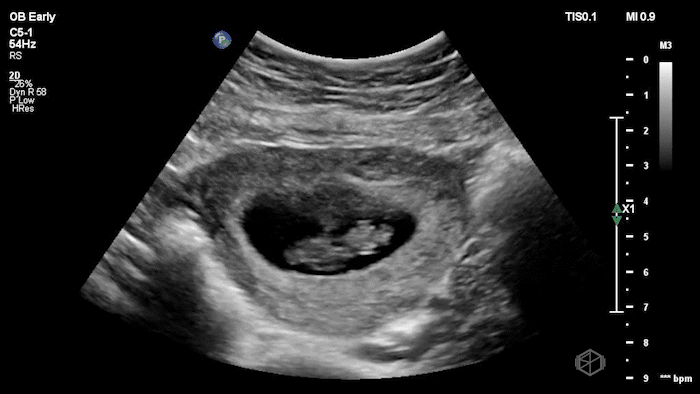

04 - What is the most likely diagnosis and definitive next step for this patient?

Left adnexal complex mass with significant free fluid concerning for ruptured ectopic pregnancy (OB Early setting).